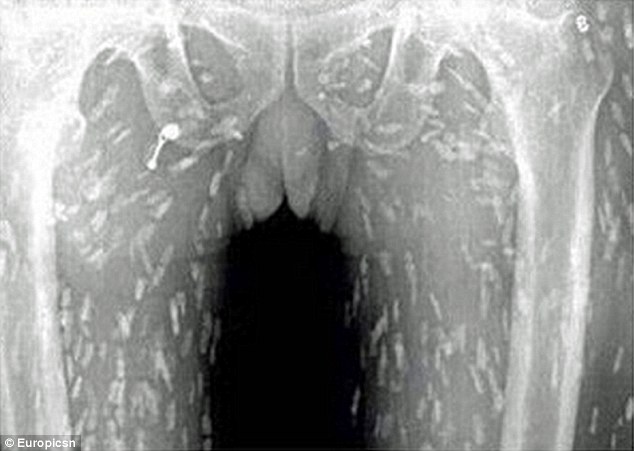

Ảnh scan cho thấy toàn bộ cơ thể của người đàn ông bị nhiễm sán dây

Ảnh scan cho thấy toàn bộ cơ thể của người đàn ông bị nhiễm sán dây sau khi anh ta ăn quá nhiều sashimi, cụ thể là những lát cá sống.

Bác sĩ tin rằng các món ăn Nhật chưa nấu chín này đã bị nhiễm bẩn.

Nhiễm trùng sán dây xảy ra sau khi người bệnh ăn ấu trùng của sán cá diphyllobothrium, loài sán được tìm thấy trong nhiều loài cá nước ngọt như cá hồi.

Bác sĩ Yin tại bệnh viện nhân dân số 8 cho biết việc ăn thức ăn nhiễm trứng sán dây có thể gây bệnh ấu trùng sán dây lợn – khi sán trưởng thành xâm nhập vào máu người. Kiểu nhiễm trùng này đe dọa mạng sống khi sán chui lên não.